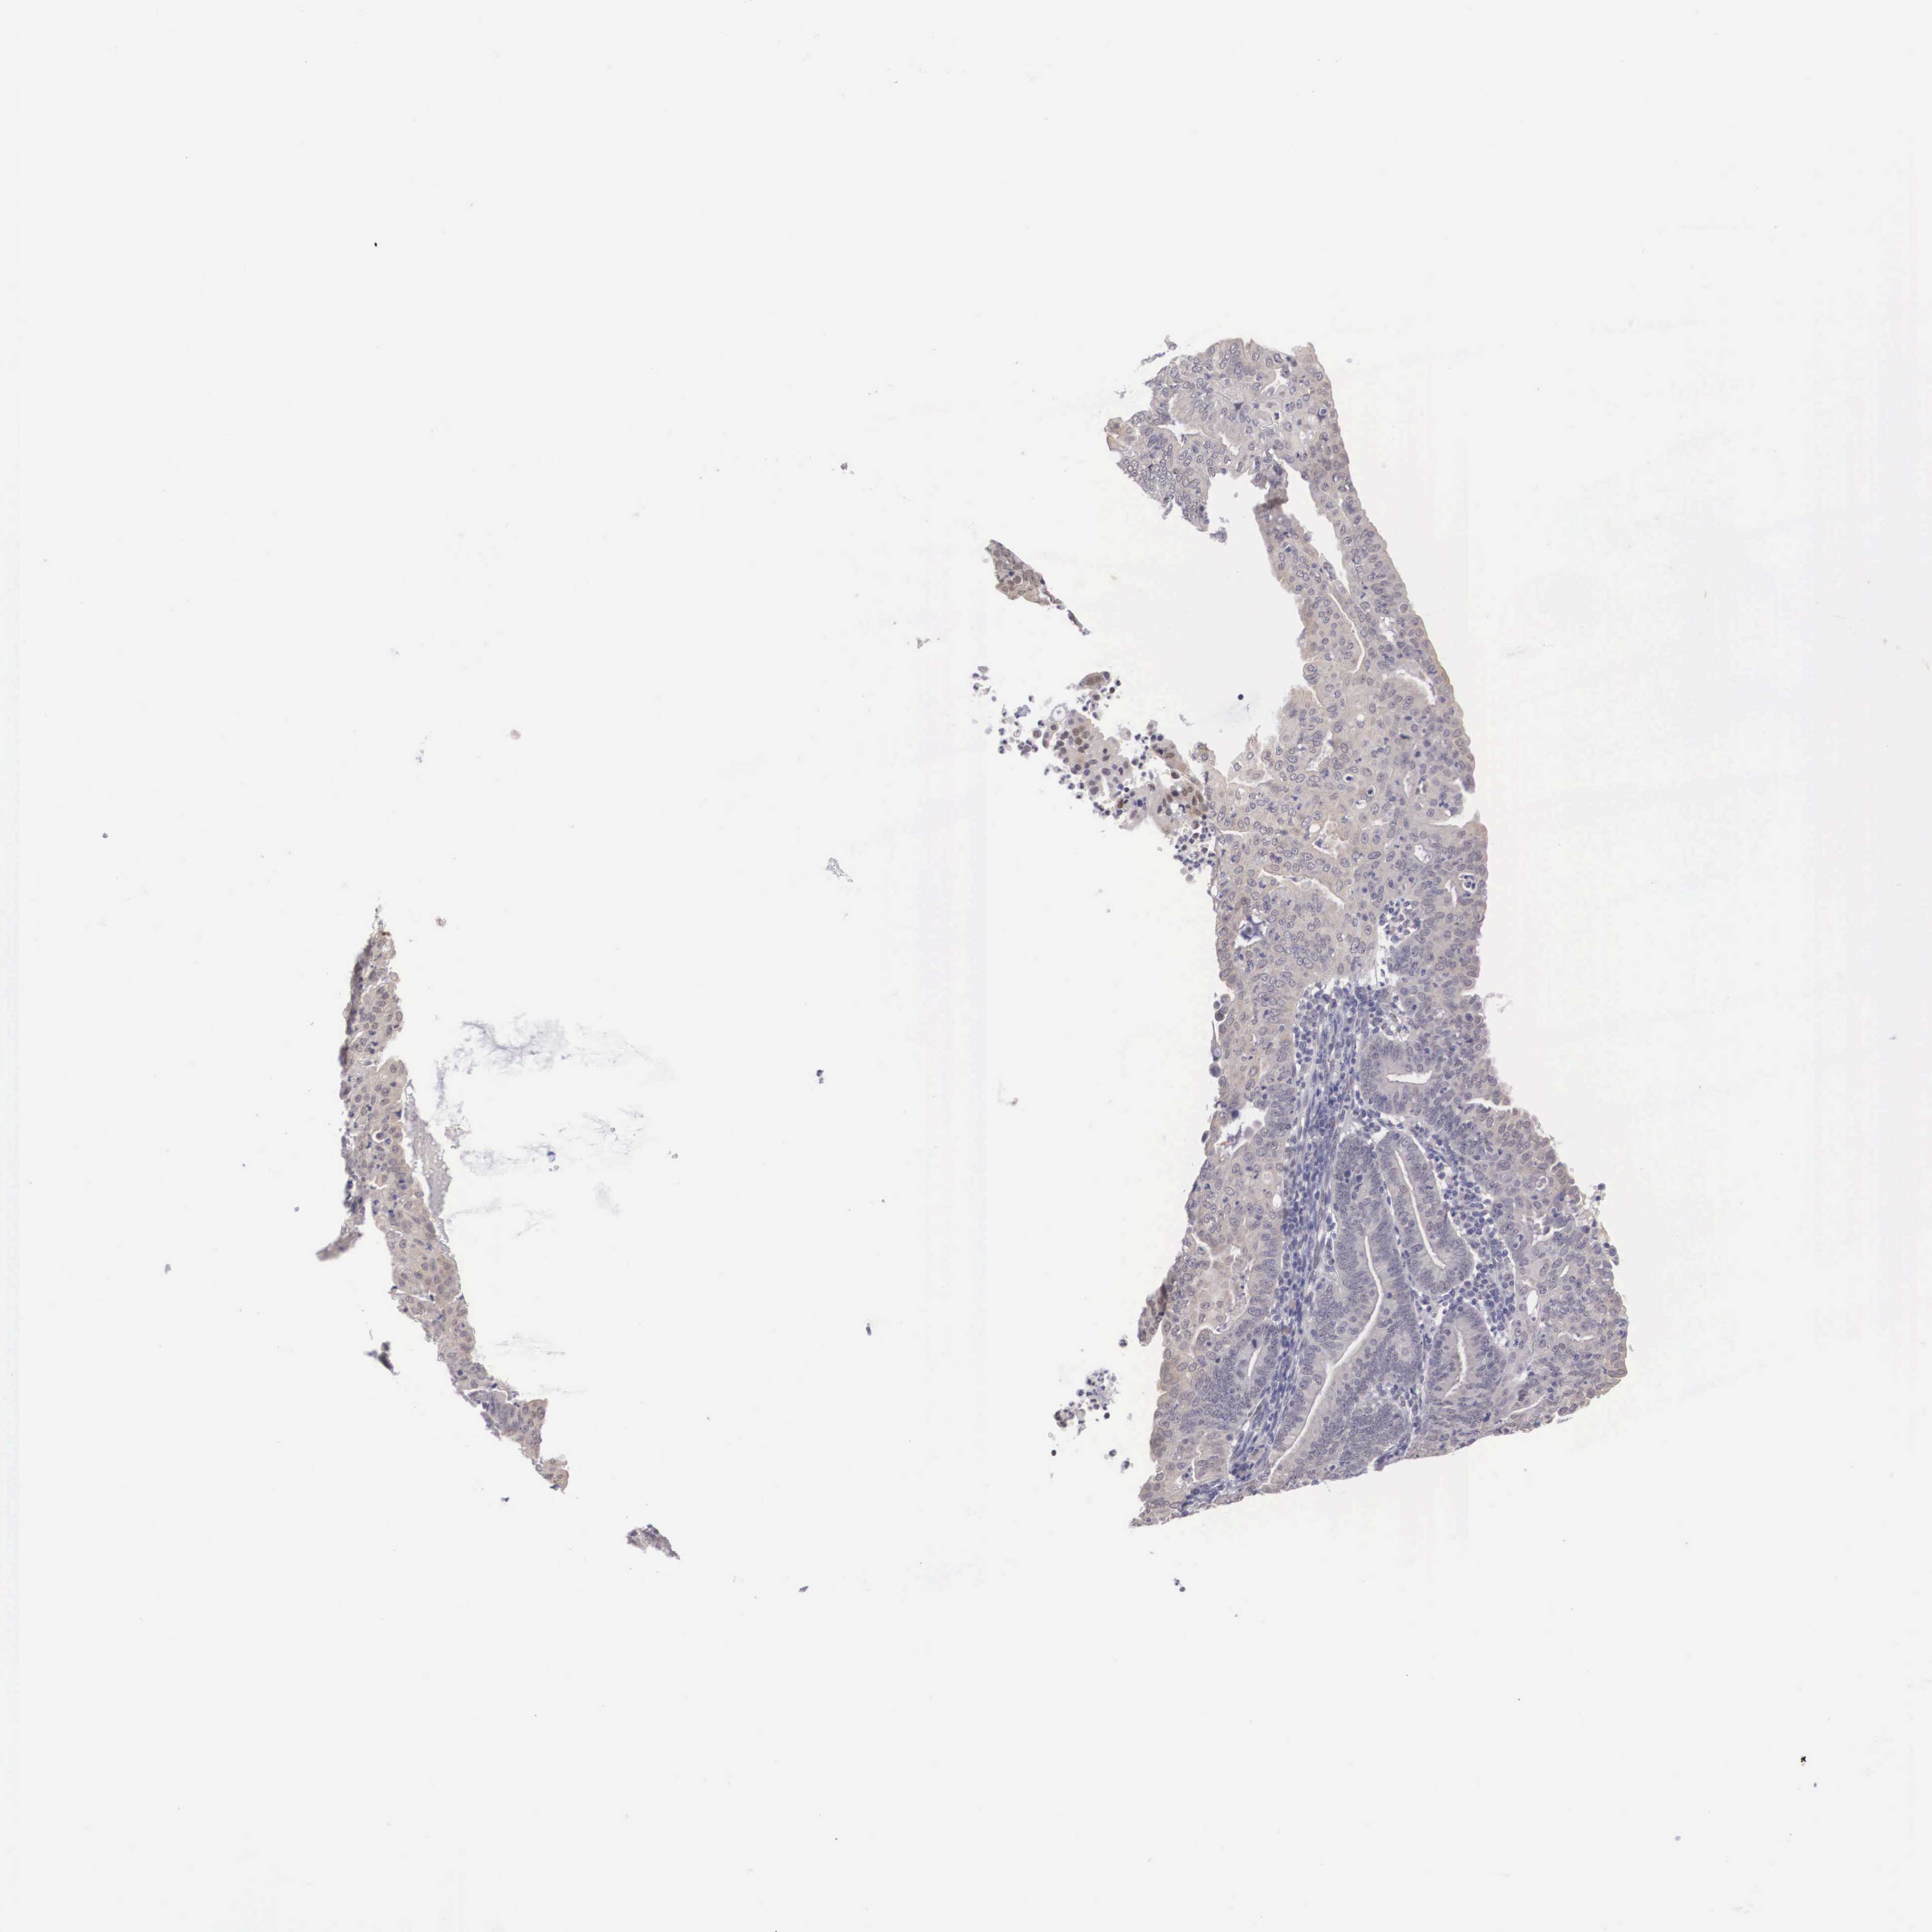

ENDOMETRIAL CANCER - Protein expressioni

A mouse-over function shows sample information and annotation data. Click on an image to view it in a full screen mode. Samples can be filtered based on level of antibody staining by selecting one or several of the following categories: high, medium, low and not detected. The assay and annotation is described here.

Note that samples used for immunohistochemistry by the Human Protein Atlas do not correspond to samples in the TCGA dataset.

Antibody stainingi

Antibody staining in the annotated cell types in the current human tissue is reported as not detected, low, medium, or high, based on conventional immunohistochemistry profiling in selected tissues. This score is based on the combination of the staining intensity and fraction of stained cells.

Each image is clickable and will lead to virtual microscopy that enables deeper exploration of all samples and also displays staining intensity scores, fraction scores and subcellular localization as well as patient and tissue information for each sample.

Antibody HPA000686

Staining

High

Medium

Low

Not detected

Intensity

Strong

Moderate

Weak

Negative

Quantity

>75%

75%-25%

<25%

None

Location

Nuclear

Cytoplasmic/membranous

Cytoplasmic/membranous,nuclear

Adenocarcinoma, NOS